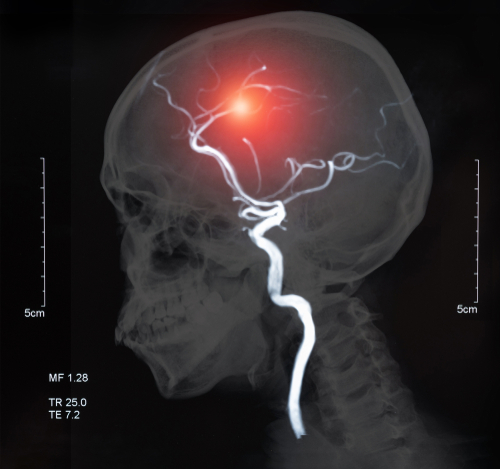

Neurolutions IpsiHand 助力偏瘫患者中风康复

Neurolutions IpsiHand 可帮助偏瘫患者进行中风康复 大约 77% 的新发中风病例会出现偏瘫,并且通常会持续到慢性中风...